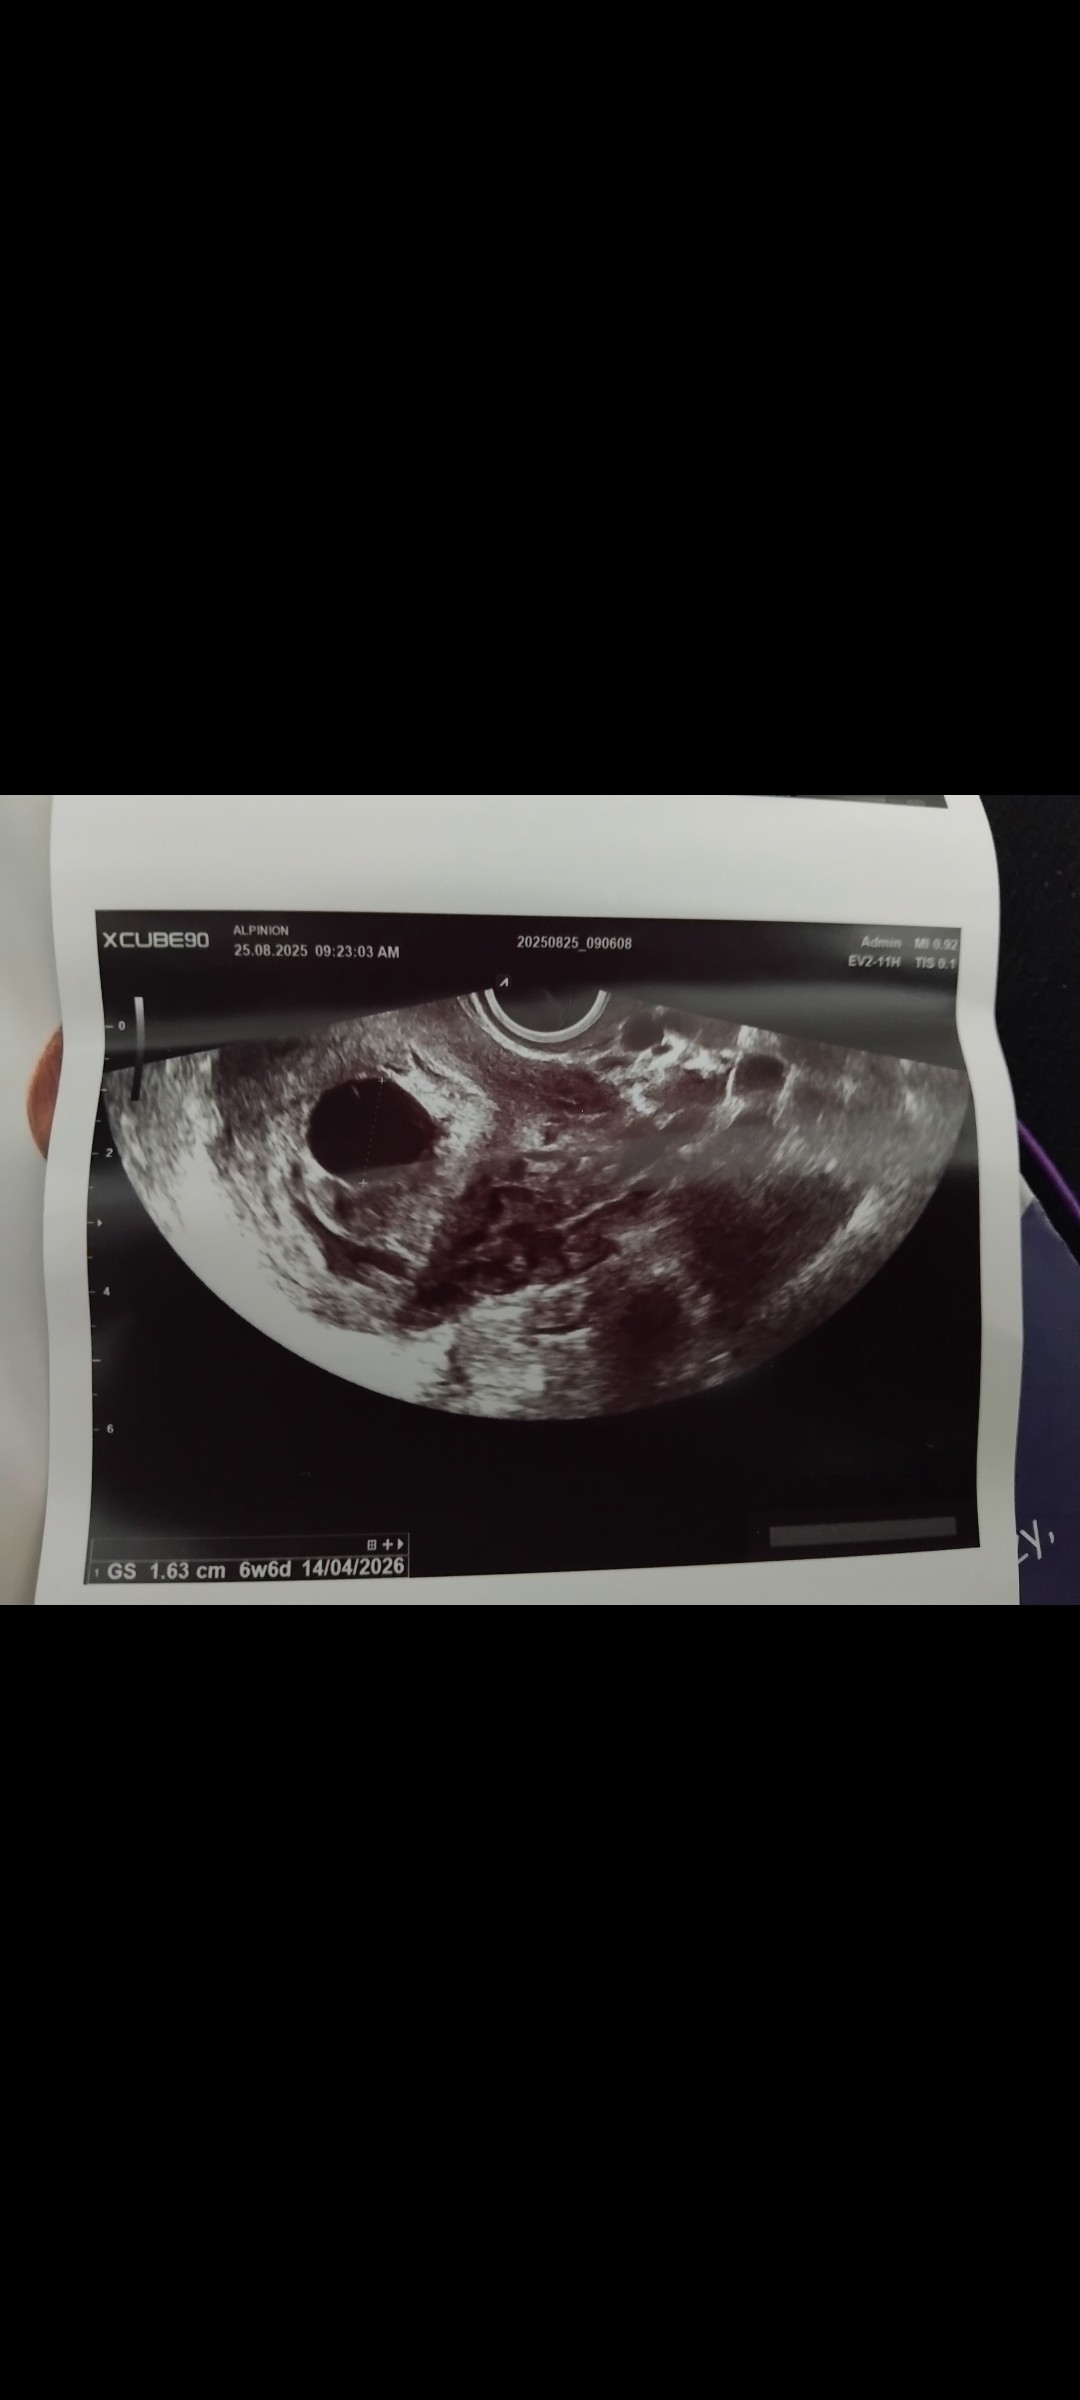

Dziś 25 sierpień kolejna wizyta pecherzyk ciążowy aktualnie ma 1.63 zarodka Dalej Brak